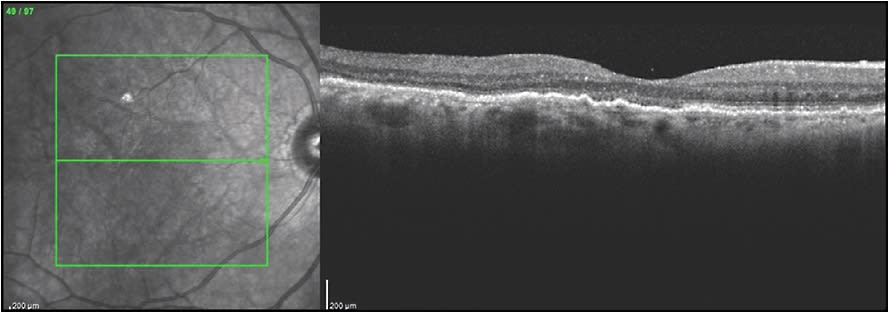

Another modality capable of assisting in the diagnosis of PCV is B scan OCT. A B scan OCT shows the polypoidal lesions as inverted U-shaped elevations of the RPE with steep borders and a gradual slope at the top of the RPE elevations.3,4 The branching vascular network (BVN) is seen as a “double line sign,” which represents a slight elevation of the RPE above Bruch’s membrane by the vascular network.15 The usual B scan OCT on most spectral-domain OCT (SD-OCT) machines is available in most practices, and can be helpful to diagnose PCV by imaging the inverted U-shaped elevation of the RPE with heterogeneous reflectivity.3,4 The polypoidal lesions can be imaged on B scan OCT in PCV cases confirmed on ICGA with the SLO in 57% of cases.16 However, these lesions are decreased after anti-VEGF therapy, so if B scan OCT is used to diagnose PCV in an anti-VEGF-resistant case, it is important to look at the B scan prior to treatment because previously imaged polypoidal lesions will be lost in 56% of cases.16 A recent study by the Asia Pacific Ocular imaging Society showed that SD-OCT findings can a have high degree of accuracy of diagnosing PCV when using 3 criteria: (1) a ring-shaped lesion underneath the RPE, (2) en face OCT complex RPE elevation, and (3) a sharp-peaked inverted U-shaped PED with an accuracy of 82%.17

Findings other than the imaging of polypoidal lesions alone are also helpful to suspect the diagnosis of PCV. Retinal pigment epithelial detachment is a frequent finding associated with PCV,4,6,12-13 and the RPED may mask the aneurysmal lesions, especially with the usual hypofluorescence and decreased visibility of hyperfluorescent lesions within the RPED when using the SLO. Polypoidal choroidal vasculopathy lesions often appear at the edge of the RPED or at a notch in the RPED (Figure 1). There is often a BVN with a double line sign connecting to the polypoidal lesions (Figure 2).14